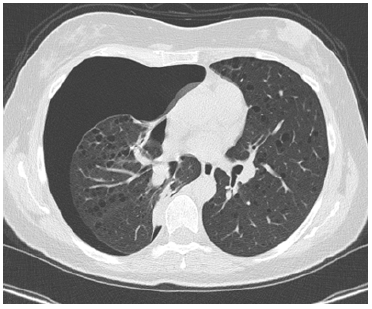

After ECG (normal sinus rhythm) and routine biochemical profiles (within normal limits) was subjected before to chest X-ray (large right-sided pneumothorax) and then to CT-scan to investigate secondary causes of pneumothorax which showed innumerable thin-walled cysts throughout both lungs (Figures 1,2) and angiomyolipoma in the left kidney.

Figure 2: Ct of the chest showing multiple thick walled cysts located throughout both lung parenchyma.

While the radiological evidence was suggestive of LAM, we preferred to do a small wedge resection of the lung because there was a persistent air leak and for certainty of the diagnosis because the appearance of diffuse pulmonary cysts indicates possible LAM but many conditions can mimic the pathology including pulmonary Langerhans cell histiocytosis, emphysema, follicular bronchiolitis, lymphoid interstitial pneumonia and advanced interstitial lung disease [2,4]. Chemical pleurodesis with talc completed the procedure. After one year the patient had no further episodes of pneumothorax and is in therapy with sirolimus with follow-up from her pulmonologist every six months.